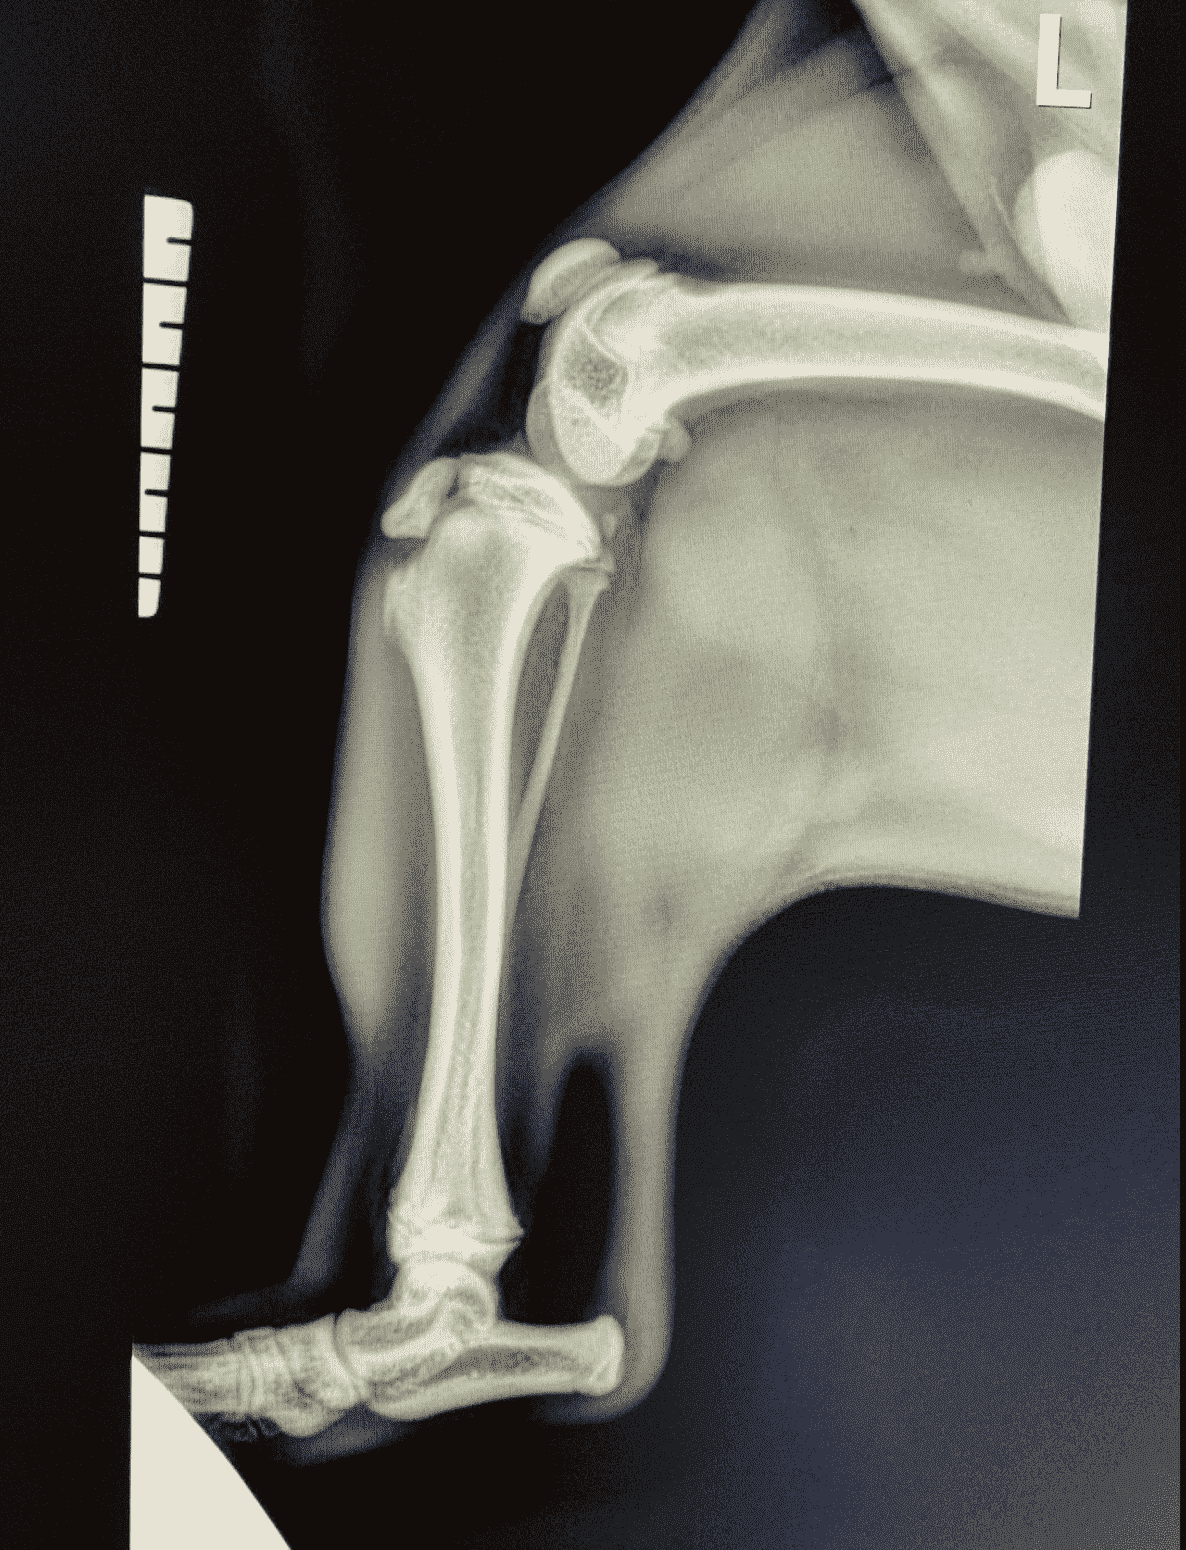

A young French Bulldog puppy named Fred presented to our clinic with a history of sudden right hindlimb lameness (limping). The owners didn’t see any major trauma, but they think he might have tried to jump up onto the bed and missed.

When examining the puppy, his right stifle (knee) was painful and swollen. The next steps included x-rays to investigate the limping.

We performed x-rays which revealed the puppy had fractured his tibia (bone in the leg). The specific fracture area was the tibial crest, which is prone to fracturing in young dogs if they hurt their stifle. See the x-rays attached, right and left stifle, for comparison.